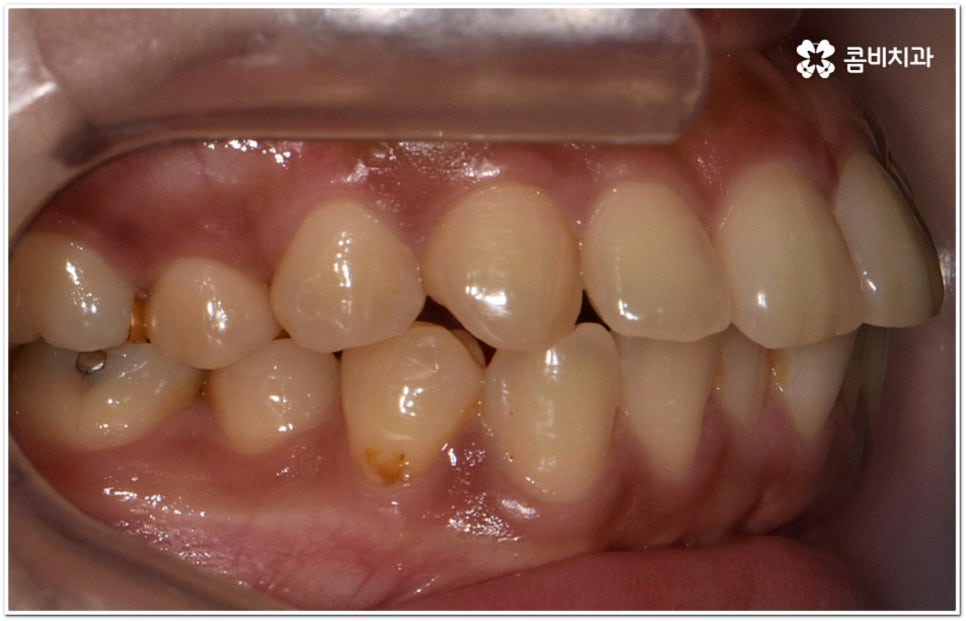

옆에서 봤을 때 코나 턱보다 입이 더 튀어나와 있으면 뾰루퉁한 인상을 줄 수 있고 웃을 때 잇몸이 드러나 콤플렉스처럼 느껴질 수 있는데요. 정도가 심한 경우 입을 꼭 닫고 있기 어려워 자기도 모르게 구호흡을 하게 되면서 여러 구강 질환 및 구취를 유발하게 될 수도 있기 때문에 이러한 심미적 또는 기능적인 이유로 돌출입교정치과 를 알아보시는 분들이 많이 있을 거예요.

이때 위아래 치아가 맞물리는 데는 별다른 문제가 없고 앞니 등 치아가 조금 뻐드러진 상황이라면 각도만 개선해도 되지만 잇몸뼈 자체가 나와 있고 교합에도 문제가 있다면 종합적인 해결이 필요할 수 있는데요.

단순히 치아가 튀어나온 각도를 고친다고 돌출입 개선이 되지는 않고 구조적 골격적인 원인을 파악하여 해결해야 추후 턱관절 건강 부분에까지 좋지 않은 영향을 미치는 것을 막을 수 있습니다.

환자마다 치열, 교합, 치아가 튀어나온 각도, 잇몸이 드러나는 정도, 상악과 하악의 구조 및 관계 등 턱관절 관련 부분 상황이 모두 다르기 때문에 3D CT 같은 정밀 검진 기계를 통해 이를 꼼꼼하게 살펴보고 각각에 맞는 계획을 세밀하게 세워 교정 치료를 진행해 줄 필요가 있어요. 이때 환자분들의 상황에 따라 양악수술과 같은 외과적인 방법을 병행해야 하는 케이스도 있을 수 있기 때문에 돌출입을 가지고 계신 분들 중에서 수술에 부담을 느끼고 지레 치료를 포기하신 분들도 있을 수 있는데 정도가 많이 심각하지 않고 구조적인 원인이 크지 않다면 대부분의 케이스는 치아교정 만으로도 충분히 개선이 가능하니 먼저 돌출입교정치과 에 들러서 정밀 검사를 진행한 후 치료 방향에 대해 의료진과 논의해 보시면 좋을 거예요.